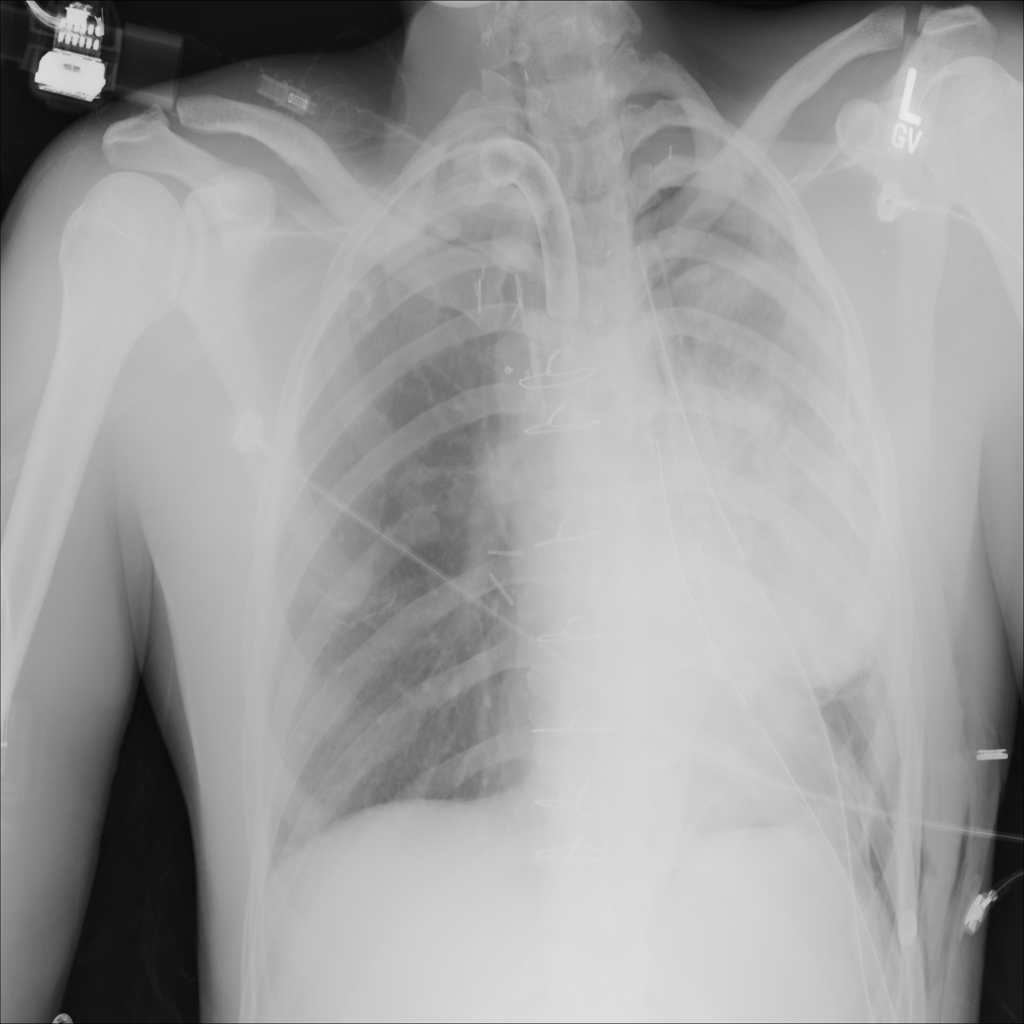

Showing up to 90 reference images for Pneumothorax.

PAT-9AC1 · IMG-005Pneumothorax

PAT-9AC1 · IMG-005

AP